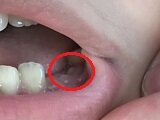

食事に密に関係するクチ・歯のコト。 久しぶりに歯が抜けました。

奥歯が抜けて、生えてきました

左、下、奥。

抜ける歯があれば、生えてくるわけですが、左、上、前、横にはえてきちゃいました.....。

横に生えてきちゃいました

イャイャ、コレは非常に懸念。 矯正はできないもんなぁ.....。

その他にも、揺れてるのがあるそうです。

ガンガン噛んででます

最近、また噛み癖が出てきたと思ってたんだよなぁ.....。

まだまだ続きそうです.....。